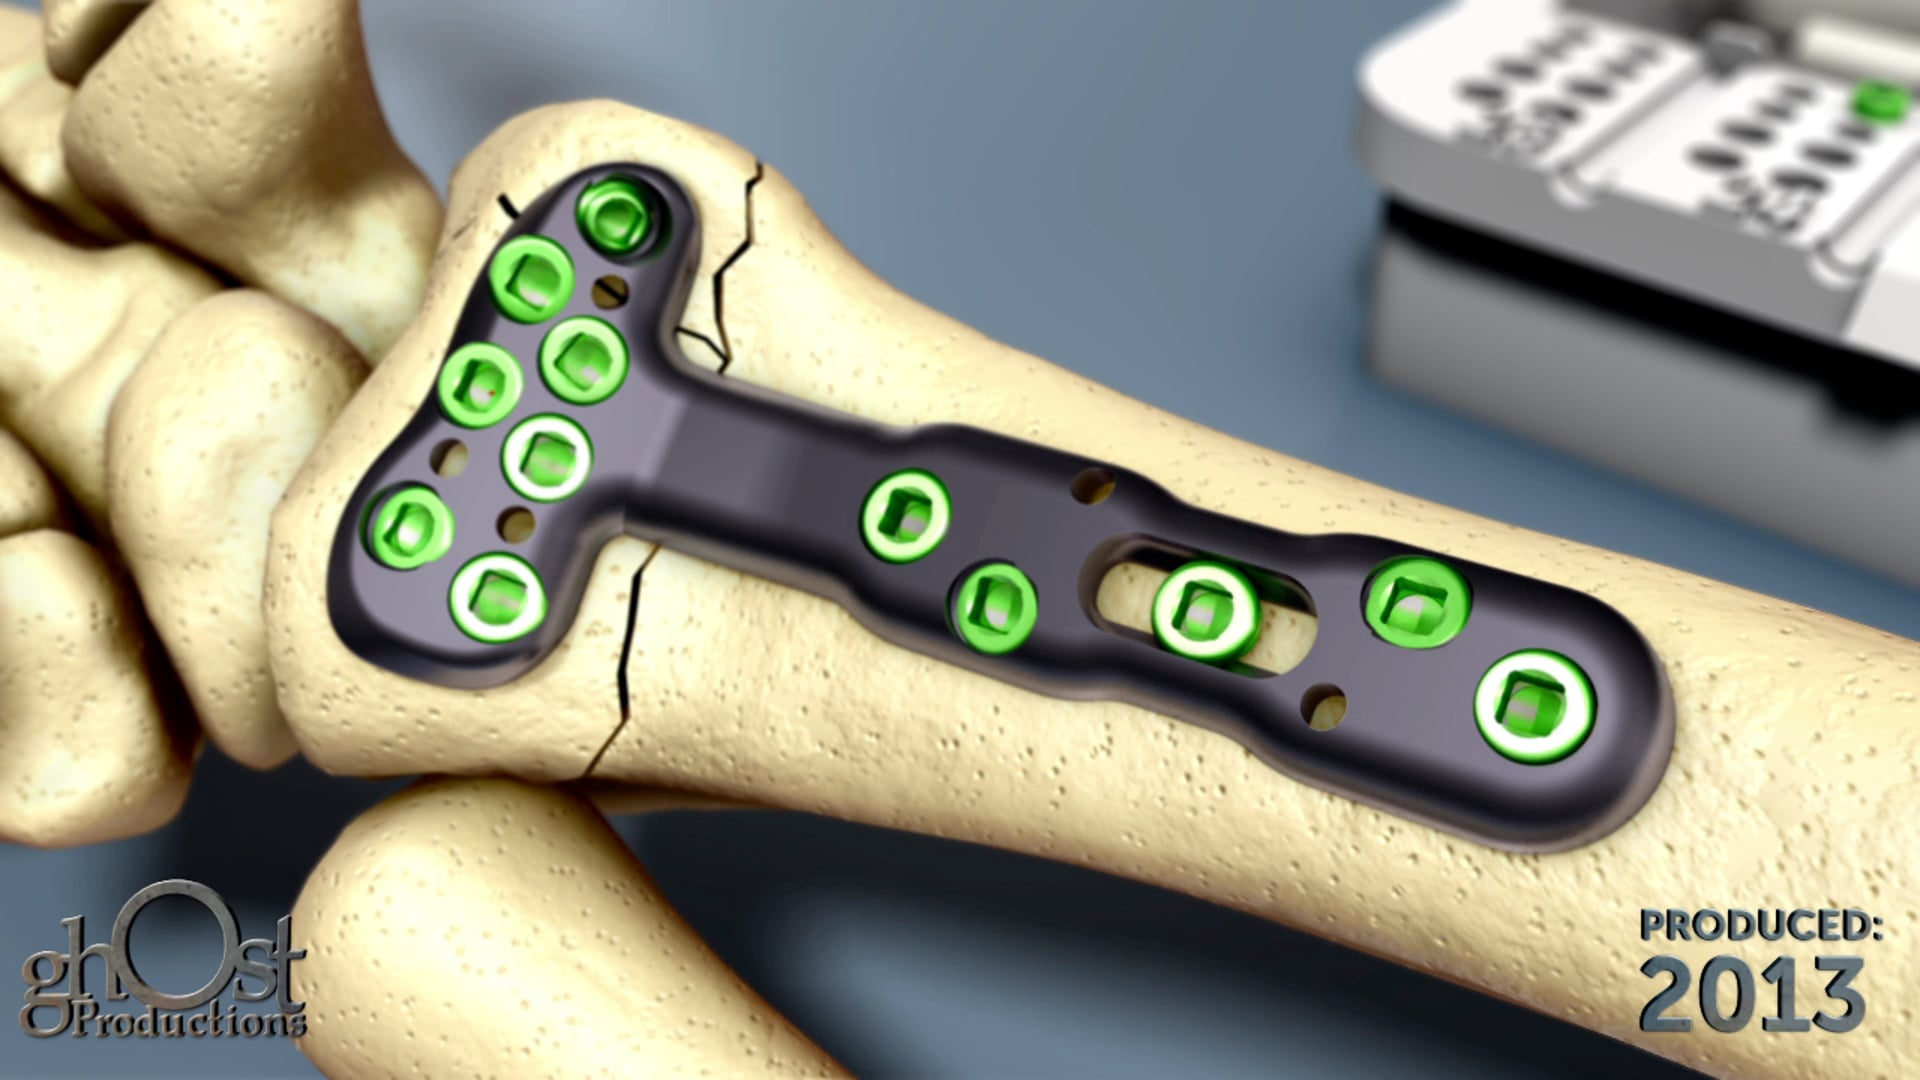

Ghost Productions showcases Biomet's ePAK DVR Crosslock Distal Radius plating system, designed to simplify treatment of distal radius fractures.

In this medical animation, created by Ghost Productions for Biomet, the innovative ePAK DVR Crosslock Distal Radius plating system is showcased. This cutting-edge product is designed to simplify the treatment of distal radius fractures, a common injury that can be challenging to address. The ePAK DVR offers advanced fixation options and streamlined instrumentation, making it easier for medical professionals to provide effective care to their patients. This animation is a valuable resource for anyone in the field of orthopedic medicine, and highlights the benefits of Biomet's state-of-the-art product.